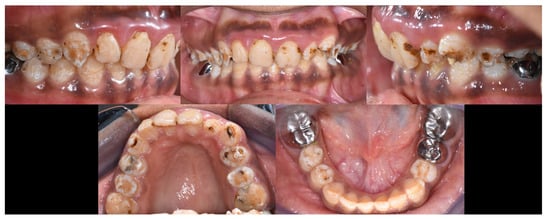

2.2. Clinical Examination

2.3. Radiographic Examinations

2.5. Treatment Procedure